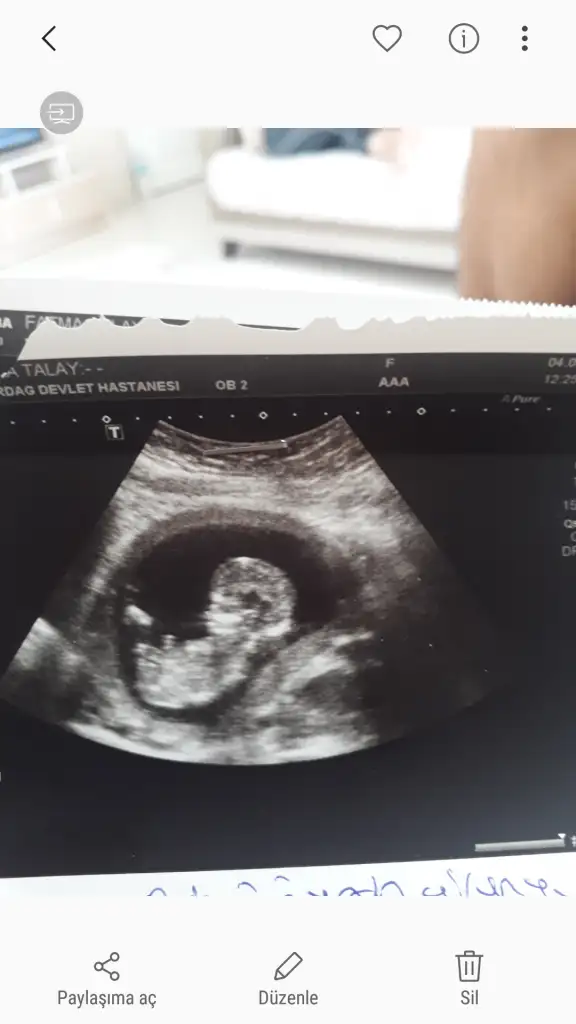

Bugün ikili test için gittiğim Dr. da kız dedi dünde erkektiKafamız cok karıştı çıkıntı düz çünkü dedi o da ama bu kadar büyük çıkıntı okuyor mu sizce ?

Usg yaniltmiyorsa ki yan donmus sanki kiz gibi bu bebisteEki Görüntüle 2307207